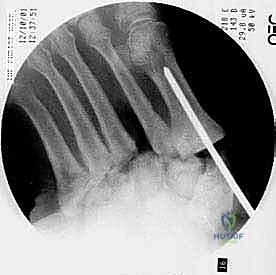

يتم استخدام أسلاك توجيهية (Guide Wires) يتم إدخالها تحت توجيه الأشعة السينية المباشرة (C-arm) من خلال عظام مشط القدم، مروراً بمفاصل منتصف القدم، وصولاً إلى عظام الرصغ (مثل العظم الزورقي أو الكاحل). بعد التأكد من المسار الصحيح، يتم استخدام مثقاب خاص، ثم تُدرج المسامير المحورية الصلبة (غالباً مسامير بقطر 6.5 مم أو 7.0 مم) لضغط المفاصل وتثبيتها بقوة هائلة.